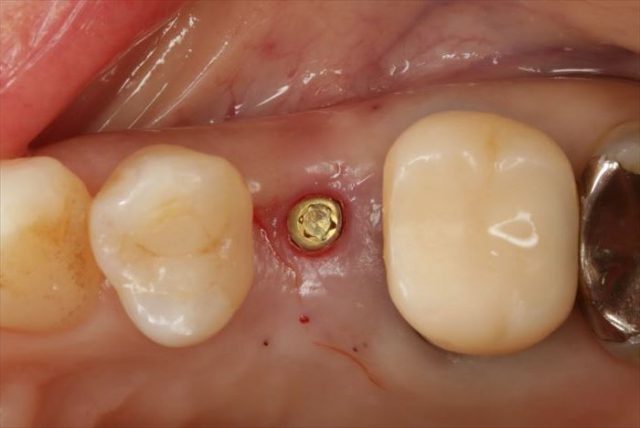

挿入ジグを外しました。

封鎖スクリューでインプラントフィクスチャーを保護します。

フラップレス埋入オペでは出血もあまりありません。

無事に終わりました。